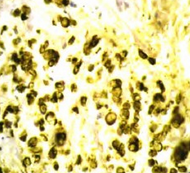

多学科会诊暂不行手术治疗,给予新辅助化疗,方案:奥沙利铂150 mg+卡培他滨1500 mg,2次/d,第1天至第14天,化疗1个疗程,行放疗25次,总剂量50 cy,放疗中期评估肿瘤未见明显缩小,排便困难加重。期间患者无意中发现左乳肿块,查体可触及左乳外下方有一约5 cm大小肿物,质硬,活动度差,无压痛,后行乳腺B型超声:左乳外下低回声性质待定,左乳内下实性结节,右乳乳晕区皮下实性结节。后行穿刺活组织检查,左乳结节穿刺病理坏死组织中可见少量印戒样细胞(图IB),考虑为黏液腺癌,结合临床考虑转移性直肠黏液腺癌可能。 MRI示:直肠窝及盆壁淋巴结转移较前略有增大,左侧腹股沟肿大淋巴结为新出现,右侧髂骨异常信号考虑为转移。PET.CT示全身多处转移。给予贝伐珠单抗400mg+奥沙利铂200mg+卡培他滨1500mg,2次/d,第1天至第14天,化疗1个疗程后出院。出院前查体,右乳腺可触及一肿物,大小约2 cm×2 cm,考虑为转移癌。1个月后因肠梗阻于当地医院行造瘘术,术后给予姑息治疗,术后4个月死亡,总生存期为9个月。